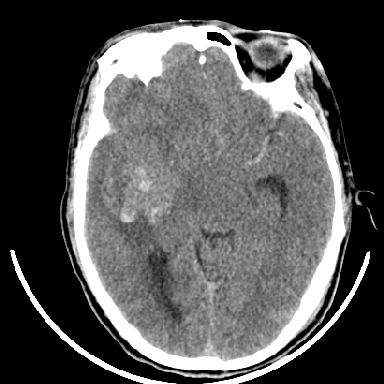

标题: CT6056:脑出血(血管畸形?) [打印本页]

标题: CT6056:脑出血(血管畸形?)

m 40突发头痛左侧偏瘫3小时

考虑高血压性脑出血,依据:

1是高血压性脑出血的好发部位,形态呈肾形,是高血压性脑出血的常见形状

2增强时占位效应加重了,考虑出血还没有停止

3病灶周围水肿不是太厉害,一般肿瘤出血水肿多非常明显

4病灶周围的‘软组织’影没有明显的强化

5至于脑血管畸形引起的出血,暂时没有看到明显的畸形血管影,也不太支持

支持右侧基底节脑出血

右侧基底节区脑出血.

支持右侧基底节区(主要为外囊区)原发性脑出血。

另附部分资料:“血液溢出血管外形成血肿,其内含有大量血红蛋白、血浆白蛋白,球蛋白,因这些蛋白对x线的吸收系数高于脑质,故ct呈现高密度阴影,ct值达40~90h,最初高密度灶呈非均匀一致性,中心密度更高,新鲜出血灶边缘不清。基底节区血肿多为“肾”型,内侧凹陷,外侧膨隆,因外侧裂阻力较小,故向外凸,其它部位血肿多呈尖圆形或不规则形”

术中抽出40ml陈旧血液,血肿底部似见一条索血管影